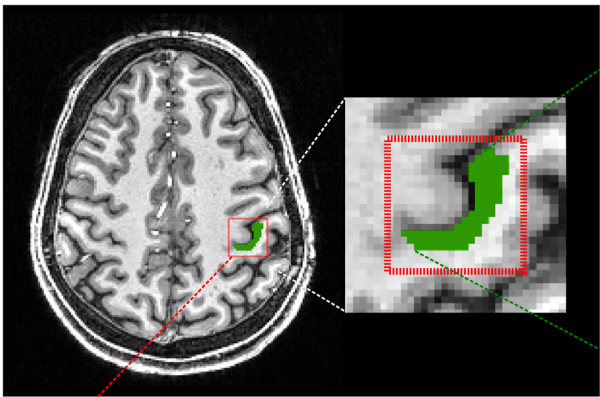

We focus particularly on the primary motor cortex (M1) and use novel Magnetic Resonance Spectroscopy (MRS) and Magnetic Resonance Imaging (MRI) to quantify local GABAergic concentrations. Our work studies the fundamental relationship between local inhibitory activity and dynamic activity as revealed using electrophysiological approaches, and to network-level connectivity as determined by MRI. In combination with these imaging approaches. we use non-invasive brain stimulation approaches to manipulate on-going activity to determine causality of the identified relationships.